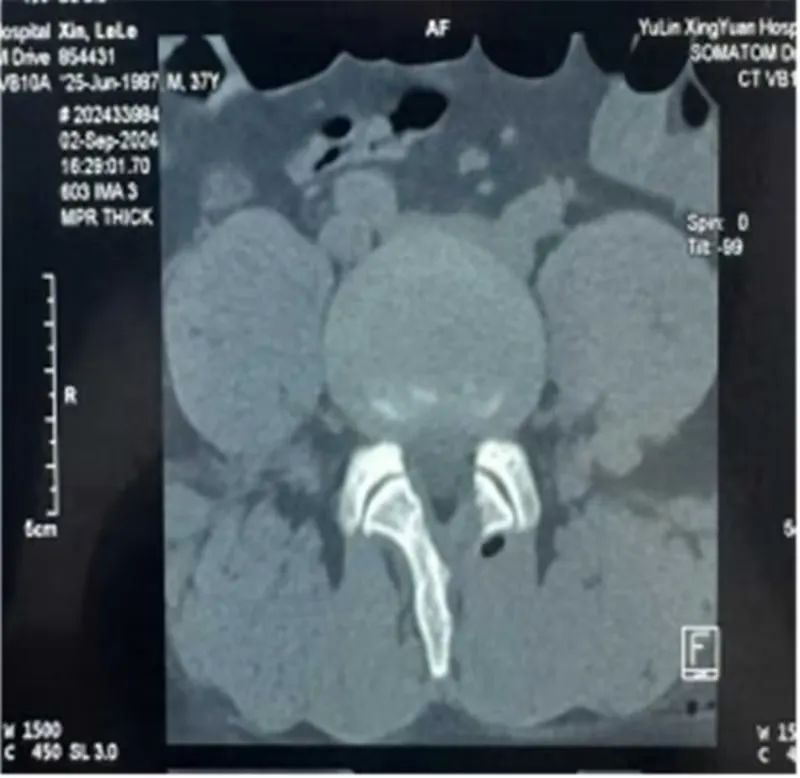

37岁的辛某某,腰臀部酸胀1年,左下肢放射性疼痛1月,曾在当地医院诊断为腰椎间盘突出症给予理疗、射频消融等治疗后症状缓解不明显,近1月来出现左下肢放射性疼痛,从臀部放射至大腿后侧、膝关节、小腿外侧,疼痛进一步加重,严重影响到患者的日常生活。不能下地活动,为寻求进一步治疗,来到市星元医院就诊。经过专科查体及影像学辅助检查,患者被诊断为腰椎间盘突出症、腰椎管狭窄症。邢永军主任医师团队综合评估患者病情,结合患者年龄、椎管狭窄程度、椎间盘退变程度、椎间隙高度等各项指标,经与患者充分沟通,开放手术创伤太大,单轴内镜受灵活性所限,不一定能够达到手术目的,“AUSS是传统脊柱手术内镜化方案,兼具开放手术和内镜手术的优势,且创伤比双通道的UBE手术更小,是目前最好的选择!,制定了“AUSS关节镜辅助单孔脊柱手术”的治疗方案。术中,医生通过可视化内镜辅助对患者狭窄的椎管进行减压、突出椎间盘进行摘除,对破裂的纤维环进行缝合,提高患者术后生活质量,术后患者恢复良好。下肢放射性疼痛完全消失。

AUSS技术即关节镜辅助单切口脊柱手术,是目前新兴的脊柱内镜技术,结合了UBE技术与孔镜技术的优点,是单轴内镜技术的延续、UBE双通道技术的改进、开放手术内镜化的体现,是将工作通道与观察通道置于同一软性切口内,具有减压范围广、操作空间大、定位简单、透视少等特点,30度关节镜,视野范围广,镜头360度自由转动,减少操作盲区;不同内镜技术的结合:关节镜的三角操作以及后路同轴内镜的同轴摆动、旋转,以及非同轴旋转技术。